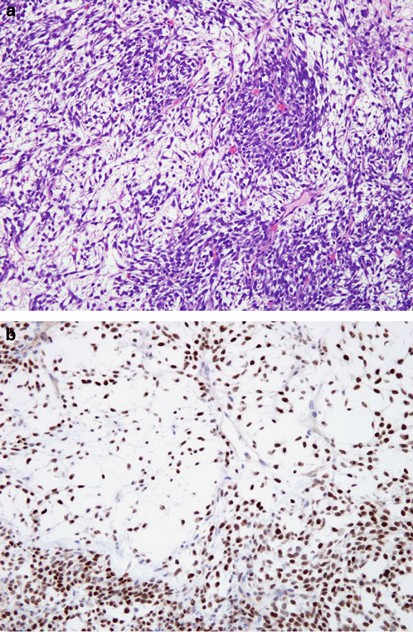

The results are summarized in Table 1. Overall, TLE1 was expressed by 18 of 20 (90%) of synovial sarcoma, with 17 cases (85%) showing 2–3+ positivity (Figures 1, 2 and 3). However, TLE1 expression was also seen in 53 of 143 (37%) non-synovial sarcoma, with 36 such cases (25%) showing 2–3+ positivity. TLE1 expression was commonly seen in peripheral nerve sheath tumors, including 30% of malignant peripheral nerve sheath tumors (Figures 4 and 5), 100% of schwannomas (Figure 6) and 33% of neurofibromas. Figures 7 and 8 illustrate TLE1 expression in other non-synovial sarcomas (alveolar rhabdomyosarcoma and myxoid liposarcoma). In TLE1-positive non-synovial sarcomas expression was often heterogenous, with some fields showing near uniform positivity, and others showing only patchy or even absent positivity. The overall sensitivity and specificity of TLE1 expression for the diagnosis of synovial sarcoma was 85 and 75%, respectively. Among non-neoplastic tissues, nuclear TLE1 expression was occasionally present in basal keratinocytes, adipocytes, perineurial cells, endothelial cells and mesothelial cells.